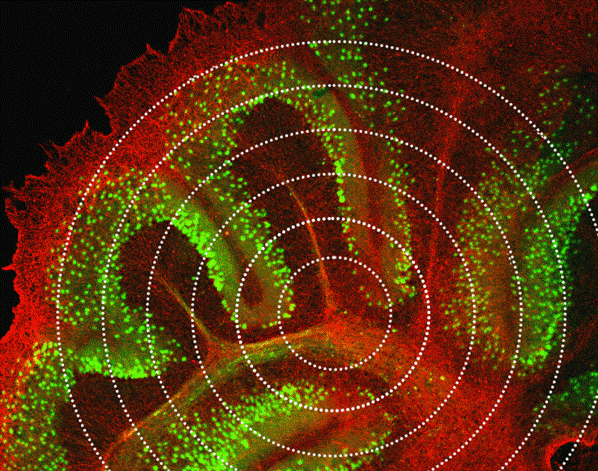

Brain tissue slice as see under the microscope.

A slice of brain tissue with fluorescent neurons under the microscope. Image credit: Merighi and Lossi, 2023.